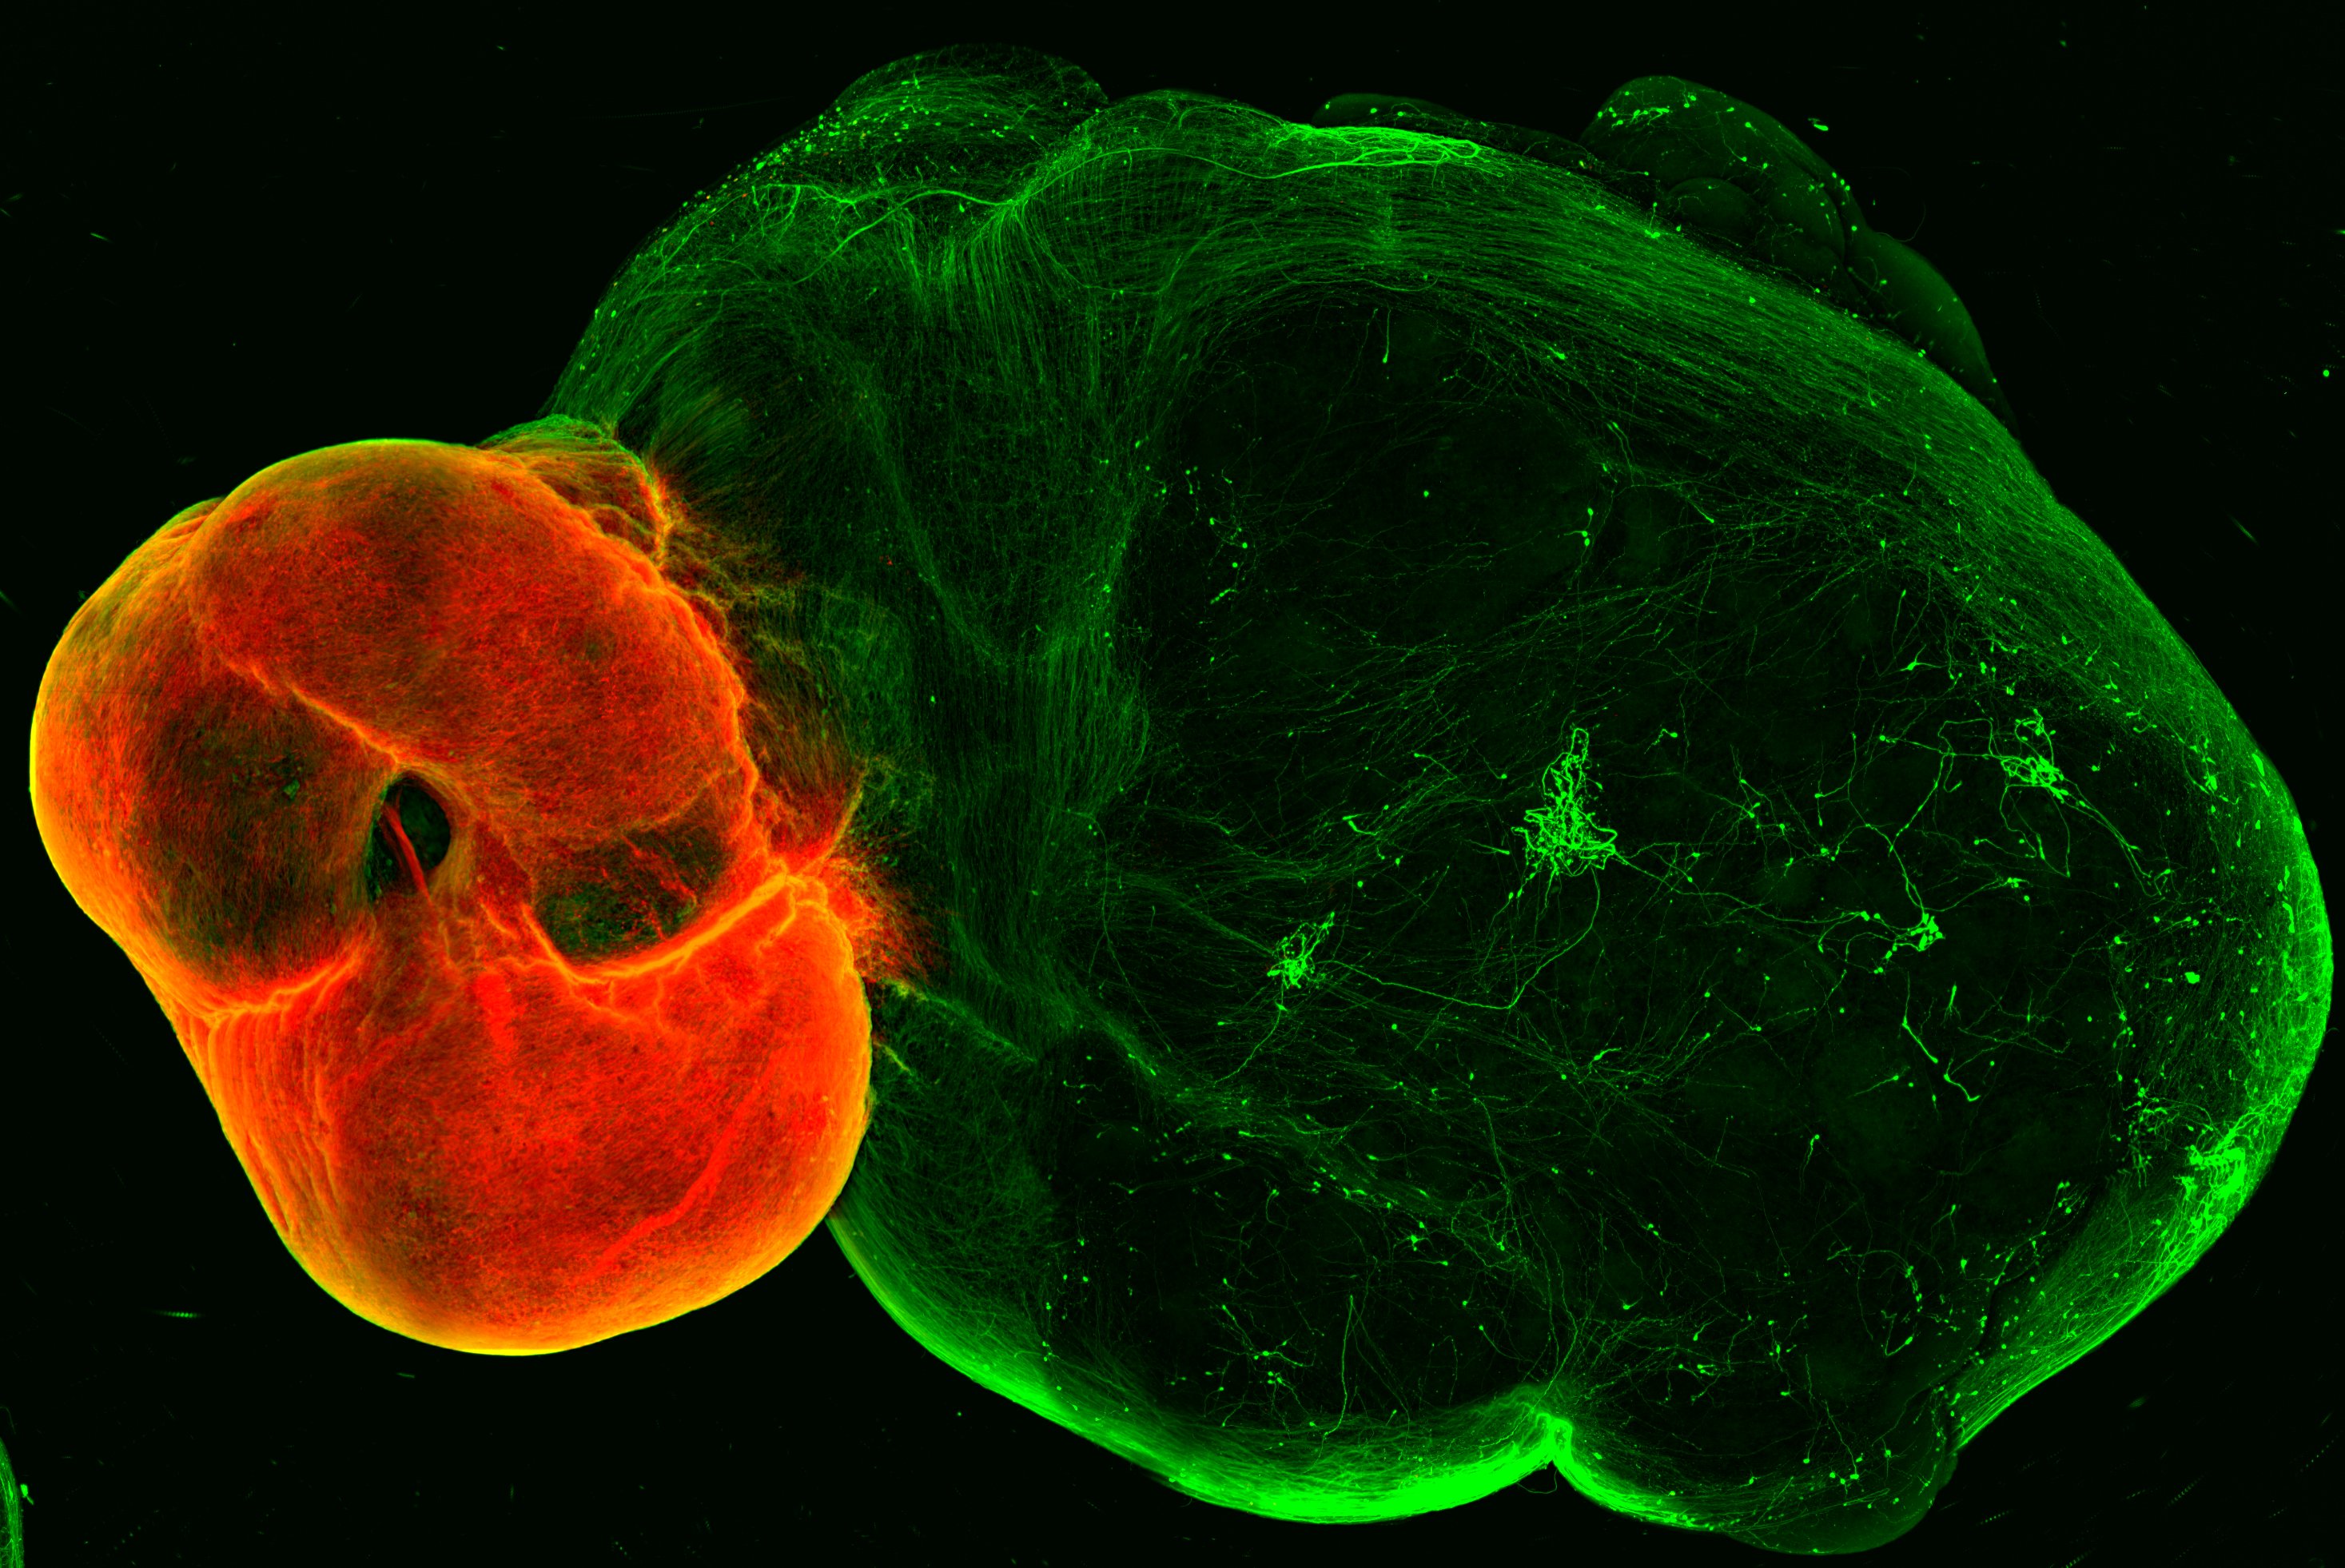

Das Team entwickelte zunächst Organoidmodelle des so genannten ventralen Mittelhirns, des Striatums und des Kortex - der Regionen, die durch Neuronen im dopaminergen System verbunden sind - und entwickelte dann eine Methode, um diese Organoide zu fusionieren. Wie im menschlichen Gehirn senden die dopaminergen Neuronen des Mittelhirn-Organoids Projektionen ins Striatum und Kortex-Gewebe aus. „Etwas überraschend beobachteten wir ein hohes Maß an dopaminerger Innervation sowie die Bildung von Synapsen zwischen dopaminergen Neuronen und Neuronen in Striatum und Kortex“, berichtet Reumann.

Um festzustellen, ob diese Neuronen und Synapsen funktionsfähig sind, arbeitete das Team mit der Gruppe von Cedric Bardy am SAHMRI und der Flinders University in Australien zusammen. Sie untersuchten, ob die Neuronen in diesem System beginnen würden, funktionelle neuronale Netzwerke zu bilden. Und tatsächlich: als die Forscher das Mittelhirn, das dopaminerge Neuronen enthält, stimulierten, reagierten Neuronen im Striatum und im Kortex auf die Stimulation. „Wir haben den dopaminergen Schaltkreis in vitro erfolgreich modelliert, da die Zellen nicht nur korrekt verdrahtet sind, sondern auch zusammen funktionieren“, fasst Reumann zusammen.